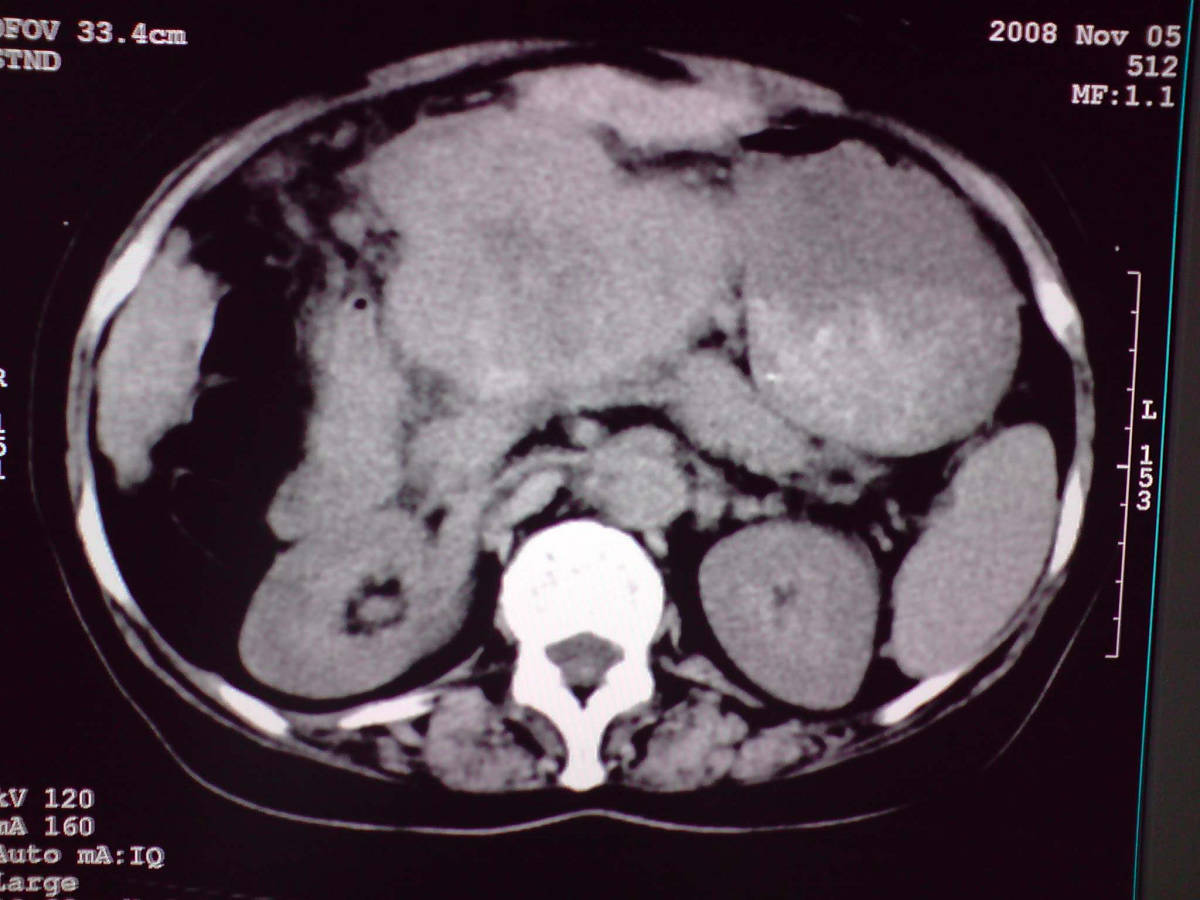

女性,60岁,上腹不适、自感胃部疼痛

小网膜区见类圆形软组织密度肿块,密度不均,内见不规则低密度区,与肝左叶分界模糊,肝脏体积缩小,密度不均匀,边缘呈波浪状,尾状叶明显增大,脾脏下缘明显超出肝脏下缘。

意见:肝硬化并外生性肝癌,建议增强扫描。

肝脏比例失调,形态失常,外缘呈波浪状,腹腔内肿块内见低密度区并与肝脏界限欠清

考虑外生性肝癌,左肺下叶占位,肝硬化

有肝硬化背景,肝胃间隙见不规则形,且密度不均匀的占位性病变,与肝左叶分界不清,首先考虑外生性肝癌可能性大,不排外肝胃间隙恶性占位肝脏受侵可能性。左肺下叶结节影,其内见空泡征,边缘见毛刺,从一元化的角度首先考虑转移。

1 肝脏各叶比例失调,形态失常,外缘呈波浪状。右叶萎缩,左叶 尾叶增大。2 腹腔内软组织密度肿块,低于肝实质密度,内见低密度区,并与肝脏界限欠清。腹膜后见肿大淋巴结,并与腹腔肿块关系密切。3 左肺下叶肿块,见边缘毛刺征及胸膜凹陷征,并与近肺门侧见异常血管相连。

综合考虑:左下肺周围性肺癌伴腹腔 腹膜后淋巴结转移!另:肝硬化!

1肝胃韧带区域一肿块,肿块上缘与肝左叶相连。肝硬化。考虑肝外生型肝癌可能性大,不除外间质瘤。2左肺下叶背段一结节,有偏心性空洞,长毛刺,其周有多发小结节。考虑结核可能性大。

感谢大家的讨论,今天拿到病理结果是肝细胞癌